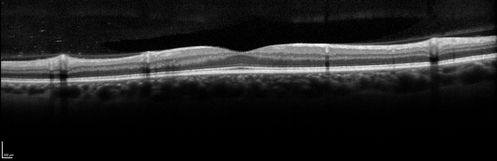

Syphillitic Optic Neuropathy and Maculopathy

46 year old woman with 2 weeks of vision loss OD.  VA 20/200 OD; 20/20 OS.  there are posterior vitreous cells on OCT in both eyes.  ICG, FAF, and FA show an abnormal macula OD.  VA improved to 20/30 within a month with treatment with PCN.